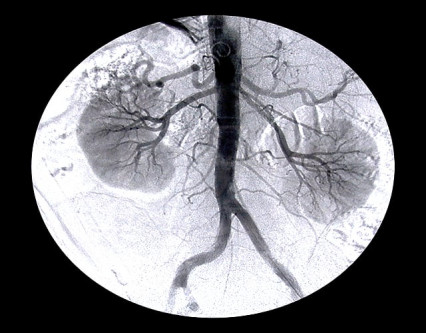

Ayesha, the complainant, told police her kidney was stolen after she was kidnapped.

Ayesha Saeed, the complainant, earlier told police that she was kidnapped by Sanaullah from Shahpur Adda in his car and taken to Noor Clinic in Sahiwal. “When I woke up, I found stitches on my lower abdomen. I learned that one of my kidneys had been removed,” she told police.